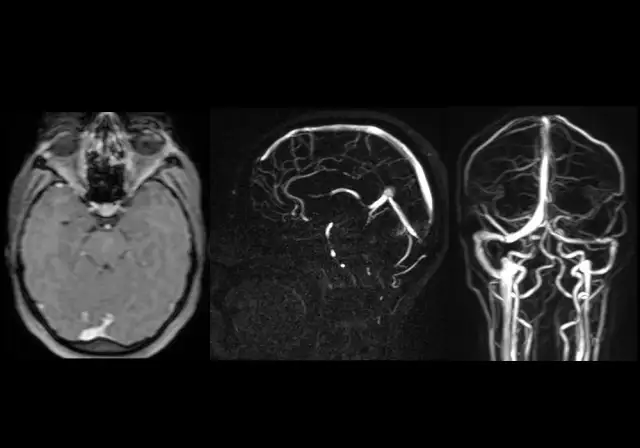

Zatoka strzałkowa górna - kluczowa rola w anatomii mózgu i zdrowiu

Zatoka strzałkowa górna odgrywa kluczową rolę w anatomii mózgu. Dowiedz się, jak wpływa na zdrowie oraz jakie patologie mogą ją dotyczyć.